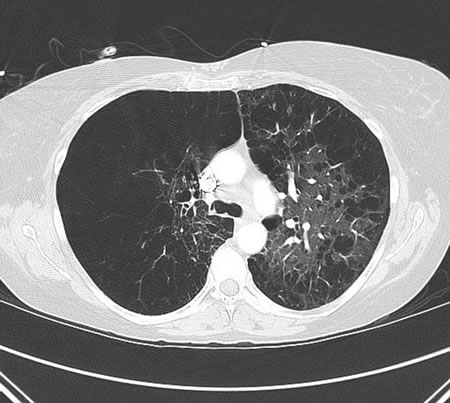

გულმკერდის CT (კომპიუტერული ტომოგრაფია)

ტესტი

გულმკერდის რენტგენოლოგიურ კვლევასთან შედარებით უკეთესად ვიზუალიზდება ფილტვის ქსოვილის დაზიანების გავრცელება და გადაბერვის ხარისხი.[Figure caption and citation for the preceding image starts]: გულმკერდის CT COPD-ის დროს: გადაბერილი ფილტვი, ემფიტემატოზური ცვლილებები და მომატებული ანტერო-პოსტერიული დიამეტრი(კასრისებური გულმკერდი)Manoochehr Abadian Sharifabad, MD -ის კოლექციიდან [Citation ends].

მოწევასთან დაკავშირებულ COPD-ისგან განსხვავებით , ალფა-1 ანტიტრიფსინის დეფიციტი მეტად აზიანებს ფილტვის ქვედა არეებს.

ფილტვების ქრონიკული ობსტრუქციული დაავადების გლობალური ინიციატივის (GOLD) გაიდლაინები რეკომენდაციას უწევენ CT-ს გამოყენებას პაციენტებთან, რომლებსაც აქვთ პერსისტენტული გამწვავებები, ფილტვის ფუნქციური სინჯებით განსაზღვრულ სიმძიმესთან შეუსაბამო სიმპტომები, FEV1 < სავარაუდოს 45% და გამოხატულია საგულისხმო ჰიპერინფლაცია, და ვინც აკმაყოფილებს ფილტვის კიბოს სკრინინგის კრიტერიუმებს.[1]

ყოველწლიური დაბალი დოზირებით CT სკანირება (LDCT) რეკომენდებულია აშშ-ს პრევენციული სერვისების სამუშაო ჯგუფის მიერ ფილტვის კიბოს სკრინინგისთვის პაციენტებში COPD-ით, რომელიც გამოწვეულია მოწევით.[66]

შედეგი

გადაბერვა